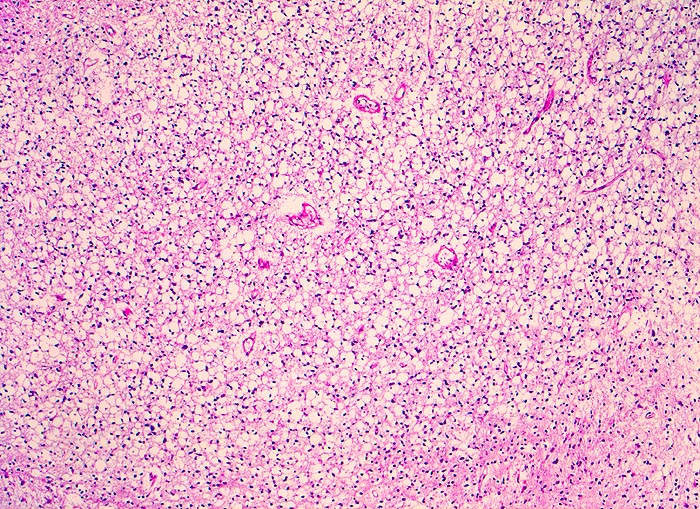

Histologisch bestehen die Oligodendrogliome aus kompakten Aggregaten runder Zellen mit deutlichen Zellgrenzen und klarem Zytoplasmasaum um einen dichten runden zentralen Kern (“Spiegelei”). Die Vakuolisierung des Zytoplasma stellt einen Fixationsartefakt dar und fällt bei Schnellschnitten als diagnostisches Hilfsmittel weg (Gefrierschnitt!). Charakteristisch sind verzweigte Kapillaren. Die Tumorzellen infiltrieren die Hirnrinde diffus und können sich bis in die Meningen ausbreiten.

• Tumorzellen umgeben von einem Halo ("Spiegeleier").

• Die Tumorzellen erinnern an Oligodendrozyten der weissen Substanz, haben aber deutlich grössere Kerne.

• Im Gegensatz zum Glioblastoma multiforme monomorphes Zellbild.